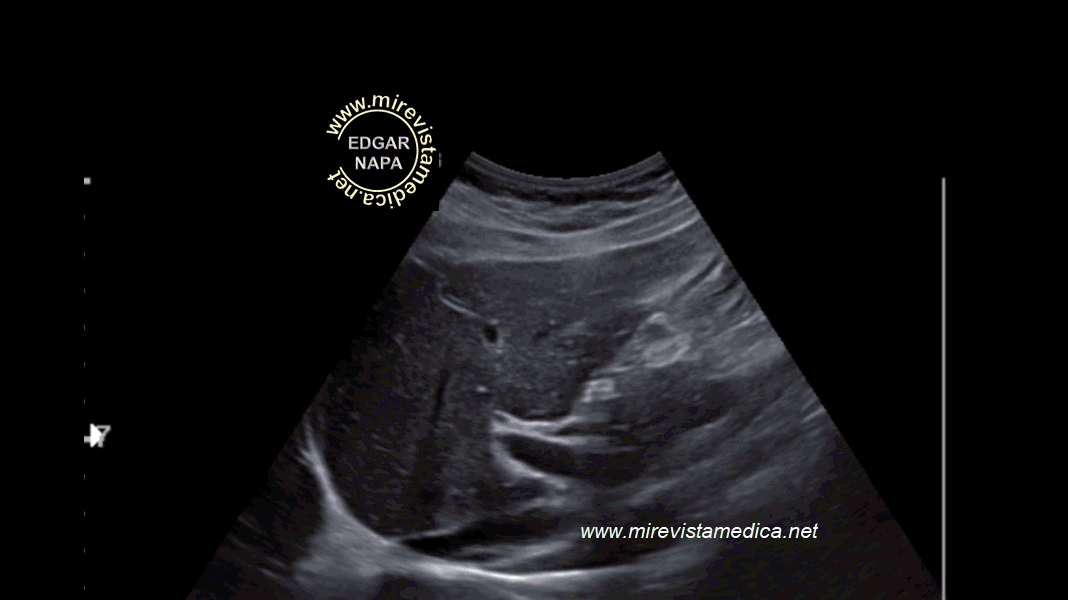

Ecografía de colédoco, incidencia sagital.

El extremo distal del colédoco normalmente no se visualiza por interposición de asas intestinales. por encima se observa la vesícula biliar.